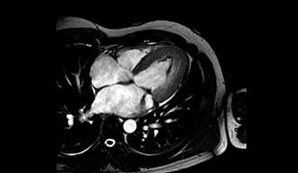

Desde el punto de vista cardiológico, solicitamos un Holter que informó ritmo sinusal con extrasístoles ventriculares y supraventriculares muy poco frecuentes, así como una RMNC con RT que informó una dilatación biauricular, cavidades ventriculares con volúmenes conservados y función sistólica global normal. El grosor de la pared libre era normal. La región apical se encontraba engrosada a expensas de depósito fibroso endomiocárdico. El realce tardío de contraste mostró una gruesa capa de fibrosis subendocárdica que comprometía todo el casquete apical y se extendía a los segmentos medios y basales de las caras inferior, inferolateral, anterolateral y septum posterior (figuras 3 y 4), músculos papilares con fibrosis extensa y válvula mitral con regurgitación grave. La ecografía renal y el Doppler renal fueron normales. Dados estos hallazgos, se completaron los análisis bioquímicos en los que se observó proteinuria de 2g/24 h.

El SAF fue descrito por primera vez en 1983,2 es una entidad autoinmune sistémica poco frecuente y se estima que un 2% de la población general la padece. Se caracteriza por la detección en plasma de anticuerpos antifosfolipídicos, como los anticuerpos anticardiolipina y el anticoagulante lúpico. Clínicamente se manifiesta por episodios recurrentes de trombosis venosa y/o arterial, trombocitopenia, abortos recurrentes y anemia hemolítica autoinmune. Se asocia con alteraciones cardiovasculares, neurológicas, renales y epidérmicas.1,3 El SAF puede ser primario cuando no existe enfermedad subyacente y secundario cuando se asocia con otras patologías, por ejemplo el lupus eritematoso sistémico. Las alteraciones cardiovasculares están presentes con frecuencia y afectan en especial a las válvulas y arterias coronarias,3,4,5 aunque también ha sido informada la presencia de trombos intracavitarios, en particular en pacientes con insuficiencia ventricular derecha.6 La fibrosis endomiocárdica es una miocardiopatía restrictiva que aún hoy tiene una etiología desconocida. Fue descrita por primera por Davies en Uganda en 1948.7Es asociado a múltiples factores etiopatogénicos como raza, clase social, malnutrición, tipo de dieta, infecciones, autoinmunidad, alergia, agentes tóxicos y herencia. Su prevalencia también es desconocida ya que tiene una distribución heterogénea, aunque su mayor localización es en África. Es la miocardiopatía restrictiva más frecuente en el mundo y afecta aproximadamente a 12 millones de personas.8,9 La asociación de SAF con fibrosis endomiocárdica es muy infrecuente. Azeem y colaboradores describieron el caso de un paciente de 50 años con fibrosis endomiocárdica con IC derecha asociada a SAF.10 Gonçalves y colaboradores informaron de un caso de trombosis biventricular en un paciente con fibrosis endomiocárdica con SAF asociado a lupus eritematoso sistémico.11 Con relación a nuestro paciente, debemos decir que al principio pensamos en una miocardiopatía hipertrófica debido a las ondas T negativas del electrocardiograma, la que luego se descartó ya que el ecocardiograma Doppler fue compatible con una miocardiopatía de tipo restrictivo debido a la dilatación biauricular con diámetros ventriculares normales, un patrón de relajación prolongada y el aumento de la ecogenicidad del endocardio, lo que sugería una fibrosis endomiocárdica que luego se confirmó con la RMNC con RT. Las imágenes de RMNC con RT se recomiendan para evaluar la estructura y la función cardíacas, medir la fracción de eyección del ventrículo izquierdo y caracterizar el tejido cardíaco, en especial en sujetos con imágenes ecocardiográficas inadecuadas, cuando no son concluyentes o cuando estén incompletos según lo recomienda la Sociedad Europea de Cardiología con una indicación clase IC.12 Es una técnica no invasiva que además de ofrecer la información anatómica y funcional que otorga la ecocardiografía aporta información adicional, así se considera a la RMNC con RT el estándar en precisión y reproducibilidad de volúmenes, masa y movimiento de la pared. Dado que la RMC ofrece una imagen de buena calidad en la mayoría de los pacientes, es la mejor alternativa para pacientes con estudios ecocardiográficos no diagnósticos. La RMNC con RT es especialmente útil a la hora de identificar trastornos inflamatorios e infiltrativos y para predecir el pronóstico en pacientes con estas enfermedades.13,14 Por otro lado, en nuestro paciente llamaba la atención la negativa de este con respecto a sus antecedentes de hipertensión arterial, pero al permanecer hipertenso durante la internación intentamos buscar otras causas del deterioro renal con proteinuria, que sumado a las lesiones neurológicas, cardíacas, a la trombocitopenia y a la detección del anticoagulante lúpico y de títulos elevados de anticuerpos anticardiolipinas permitió llegar al diagnostico de SAF primario, ya que el paciente no presentaba ninguna asociación con otra patología que justificase un SAF secundario. Las manifestaciones renales del SAF primario pueden ser agudas o crónicas y estar acompañadas de hipertensión e insuficiencia renal progresiva. La proteinuria en rango nefrótico es una infrecuente forma de presentación del SAF primario.15,16 Finalmente, si bien la ecocardiografía nos orientó en el diagnóstico fibrosis endomiocárdica, fue la RMNC con RT el estudio que perfeccionó el diagnóstico presuntivo ya que el realce tardío permitió detectar y delimitar la fibrosis subendocárdica, lo que ha sido informado previamente en algunos reportes y presenta una buena correlación histopatológica en pacientes con fibrosis endomiocárdica.17,18 Consideramos que la asociación de fibrosis endomiocárdica y SAF primario con proteinuria en rango nefrótico es extremadamente infrecuente, lo que coincide con lo encontrado en la literatura y en nuestro caso se expresó en un cuadro clínico muy complejo caracterizado por el compromiso simultáneo neurológico, cardiológico y renal.